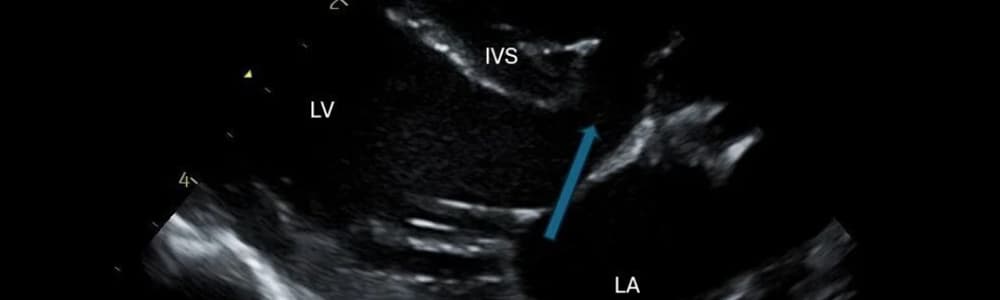

FIGURA 1 – Ecocardiografia de um defeito do septo ventricular. Onde se pode ver um defeito do septo interventricular (DSV) de grandes dimensões (seta), localizado imediatamente abaixo das válvulas atrioventriculares.

VE — ventrículo esquerdo; VD — ventrículo direito; AE — átrio esquerdo; SIV — septo interventricular.